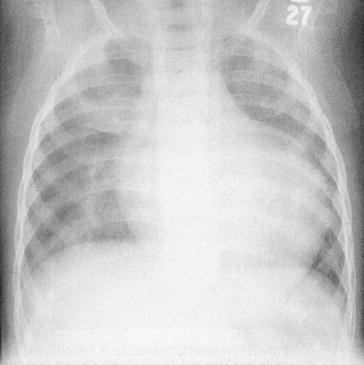

From the case Hepatosplenomegaly Xray Loading Stack 0 images remaining Xray Scroll Stack Scroll Stack Frontal The inferior aspects of both the liver and spleen are well illustrated and lie at the level of the iliac crest The heart size is considered too large when the CTR is > 50% on a PA chest xray A CTR of > 50% has a sensitivity of 50% for CHF and a specificity of 7580% An increase in left ventricular volume of at least 66% is necessary before it is noticeable on a chest xray On the left a patient with CHFDistended Neck Veins & Hepatomegaly & XRay Abnormal Symptom Checker Possible causes include Cor Pulmonale Check the full list of possible causes and conditions now!

The Radiology Assistant Heart Failure